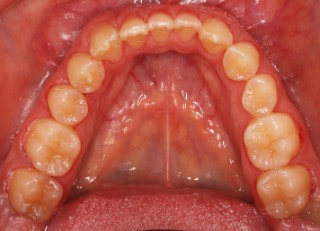

治療前